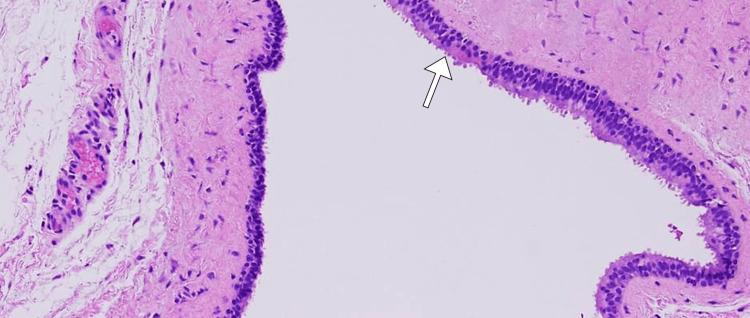

Pediatric neck masses present a diagnostic challenge, encompassing various etiologies, including rare entities like branchial cleft anomalies. Branchial cleft cysts, resulting from incomplete embryonic cleft obliteration, may become symptomatic. This case report describes a seven-year-old boy who presented with a week-long history of fever and progressively enlarging left anterior cervical swelling. Physical examination revealed a fluctuant, non-tender mass, prompting diagnostic investigations. Laboratory results indicated an elevated white blood cell count and inflammatory markers. Computed tomography identified a hypodense, rim-enhancing mass consistent with an abscess secondary to a fourth branchial cleft cyst. Ultrasound-guided aspiration yielded purulent material, confirming infection. This case highlights the clinical significance of fourth branchial cleft cysts as rare inflammatory neck masses in pediatric patients. The embryological context informs their diverse anatomical manifestations. Surgical excision remains the primary treatment, demanding consideration of anatomical complexities.